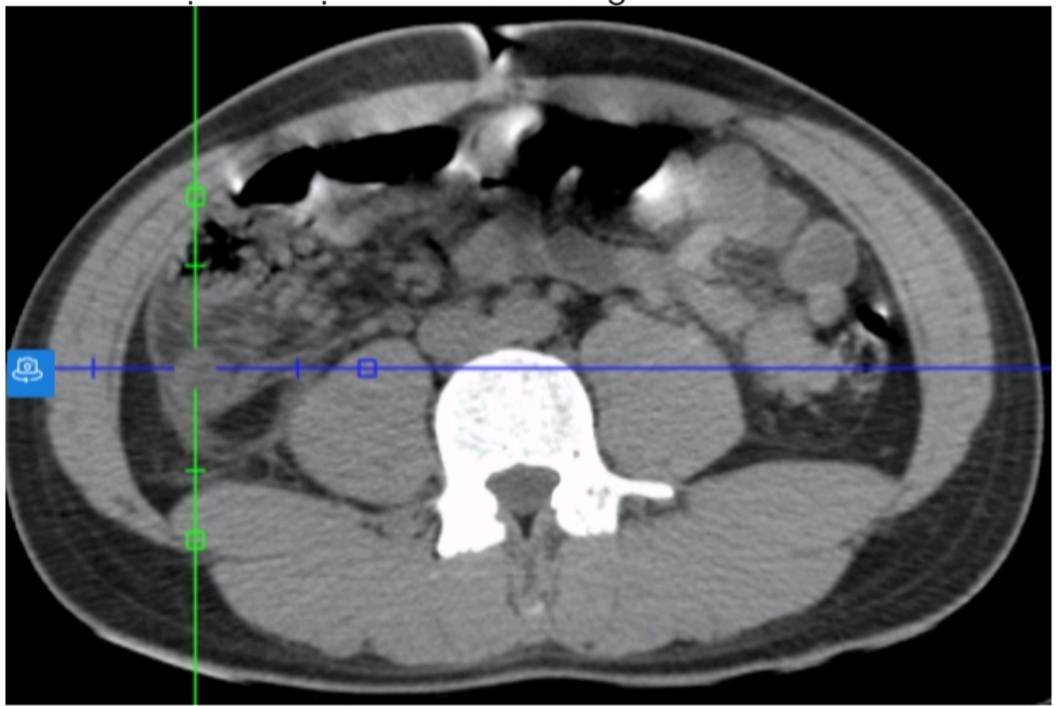

Hình chụp CT-Scanner giúp các bác sĩ phát hiện nguyên nhân gây bệnh. Ảnh: Bệnh viện cung cấp

Đến ngày 19-12, các bác sĩ đặt ra nhiều giả thuyết về ca bệnh đáng chú ý này và khám kỹ hơn, mới phát hiện bệnh nhân bị sốc nhiễm khuẩn do viêm ruột thừa hoại tử vị trí sau manh tràng. Ca bệnh này rất khó phát hiện qua siêu âm thông thường do bị ruột che khuất.

Về phía ngành y tế, bác sĩ Đặng Ngọc Dũng nhận định: Với các ca bệnh tương tự, kíp cấp cứu cần chỉ định CT-Scanner sớm. Đối với các trường hợp nhiễm trùng nặng (PCT tăng cao) mà siêu âm không tìm thấy ổ khu trú, CT-Scanner là tiêu chuẩn vàng để khảo sát các vị trí giải phẫu bất thường. Theo bác sĩ Dũng, cần cảnh giác ngoại khoa, luôn nghi ngờ viêm ruột thừa ở mọi ca đau bụng cấp kèm sốt, dù triệu chứng tại chỗ không điển hình.